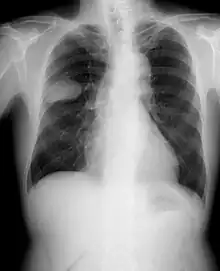

Chest X-rays are typically the first step to evaluate someone for any type of lung cancer. If images show suspicious spots on the patient's lung, a healthcare provider may order chest CT, PET, needle biopsy or bronchoscopy for further check.[32]